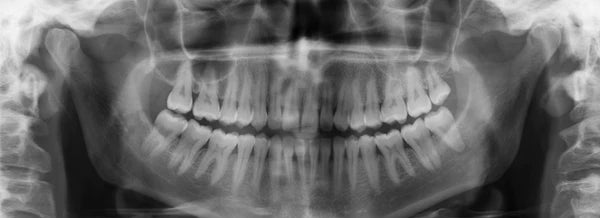

What is a dental panoramic X-ray?

In radiology, a panoramic dental X-ray allows you to take a global picture of the jaw in order to visualize the exact location of the teeth, to locate various dental anomalies, to detect dental lesions and tissues. It will above all allow the detection of dental cavities but also wisdom teeth, fractures, cysts or tumors. You can therefore have a better oral health.

Panoramic dental radiography

This technique provides an overview of the dentition, jaws, sinuses and joints. It shows all these organs in one image. It makes it possible to diagnose a large number of diseases of the mouth. The dental panoramic X-ray has its limits: it lacks precision. It just gives an overview of the organs, without really going into depth. Retroalveolar radiography targets a group of teeth and gives more precision. It is therefore considered the best. But the dental scanner is recommended to know the precise positioning of an organ.